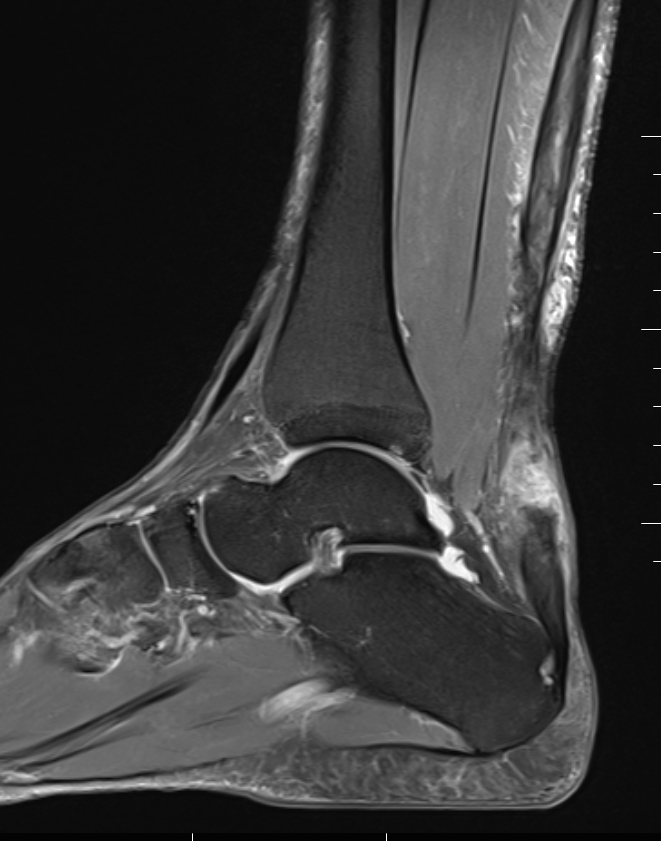

MRI

Indication

- incomplete rupture / clinical uncertainty

- chronic tears - measurement of gap for reconstruction planning

Acute

High grade partial thickness

Chronic retracted